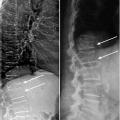

Depuis 10 ans , les appareils de densitométrie sont capables de produire une image de face et de profil du rachis lombaire et thoracique grâce à une technique appelée VFA (Vertebral Fracture Assessment, fig. 3). Ces images n’ont pas la qualité d’un cliché radiographique mais peuvent révéler une grande partie des fractures vertébrales, soit un apport diagnostique majeur. Toutefois, ces dernières doivent être confirmées par une radiographie standard (qui permet aussi de vérifier l’absence d’ostéolyse ou de recul du mur postérieur).